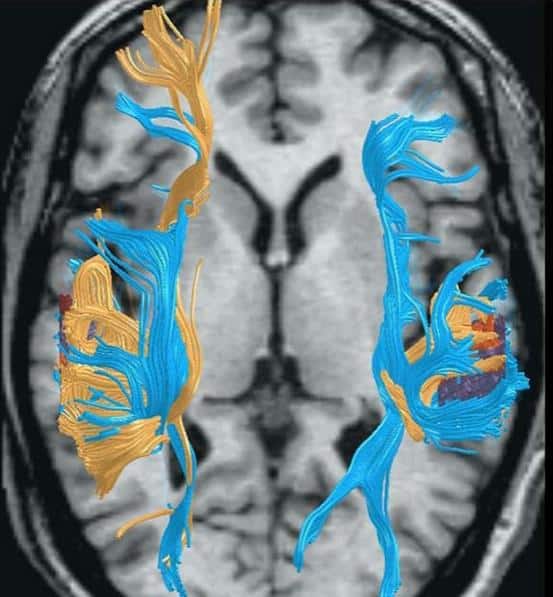

Brain Scans Show Dyslexics Read Better with Alternative Strategies

Scientists studying the brain have found that dyslexic adults who become capable readers use different neural pathways than nondyslexics. This research shows that there are at least two independent systems for reading: one that is typical for the majority of […]

When Dyslexics Become Good Readers

What Brain Science Tells us About Dyslexia and the Reading Brain. Reading well requires reliance on different mental strengths.

- Brain Function, Spell-Reading and Sweep-Sweep-Spell The importance of visual word form recognition (Issue 39)

- Brain Scans Show Dyslexics Read Better with Alternative Strategies (Issue 33)

- New Research Confirms that Dyslexics Read Better with Right Brain Strategies (Issue 75)

- The Dyslexic Brain Wired for Whole Brain Thinking (Issue 60)

- The Neural Signature of Creativity Brain Scan Explains Connection between Disorientation and the Creative Process (Issue 63)